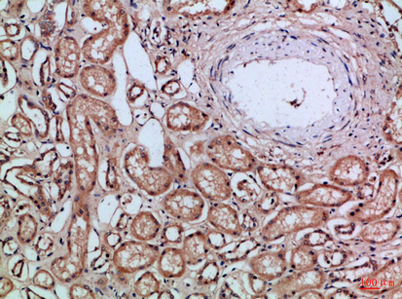

Recomended Dilution IHC-p 1:50-200, ELISA 1:10000-20000

IHC